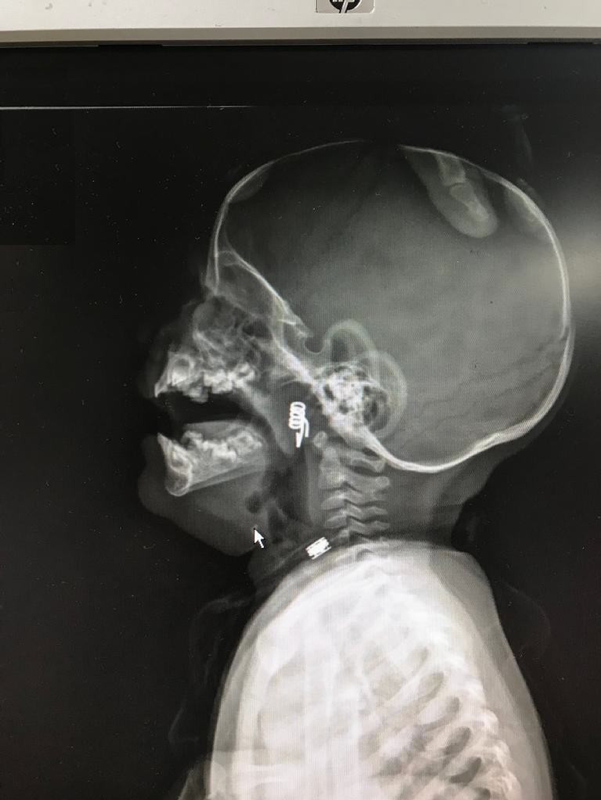

Nevşehir Devlet Hastanesi Acil Polikliniği'ne getirilen bebeği, Acil Nöbetçi doktoru Mustafa Alpaslan muayene ederek gerekli tetkikleri yaptı. Çekilen röntgen filmlerinde mandal yayının lokalizasyonu ve durumu belirlendi. Daha sonra, KBB Uzmanı Op. Dr. Ahmet Cevatzade tarafından yapılan başarılı ameliyat sonucunda bebeğin genzine saplanan mandal yayı çıkartıldı.